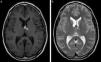

La patología trombótica también puede afectar los senos durales, generando cefalea y un posterior infarto cerebral, en muchos casos con transformación hemorrágica. El seno dural afectado (fig. 6) presenta pérdida de señal en la angio-RM y se encuentra reemplazado por material trombótico en las imágenes convencionales. El trombo venoso, asimismo, varía su señal en función del tiempo de evolución. En estos casos, otro hallazgo usual es la apertura de las venas colaterales.

Trombosis de los senos durales. La trombosis del seno longitudinal superior (flechas largas en a y b) y del seno recto (flechas cortas en a y b) evidencia imágenes (a) hiperdensas en la TC e (b) hipointensas en la secuencia GRE en corte axial. (c) La angio-RM venosa TOF, en corte sagital, muestra una señal disminuida en el seno longitudinal superior (puntas de flecha) y ausente en el seno recto-vena de Galeno (asterisco).